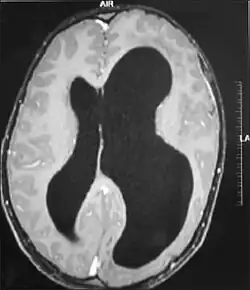

MRI images showing megalencephaly in four family members who all have unusually large skulls (the family is affected by an autosomal recessive syndrome caused by a KIF7 mutation that induces multiple epiphyseal dysplasia)[1]

Left-sided hemimegalencephaly in a person with neurofibromatosis[8]

Hemimegalencephaly is an extremely rare form of macrocephaly and is characterized by uneven development of brain hemispheres (one half of the brain is larger than the other).[9] It can present by itself or in association with phakomatosis or hemigigantism. Additionally, hemimegalencephaly will frequently cause severe epilepsy, focal neuro-logical deficits, macrocrania, and mild to severe intellectual disability.[10]